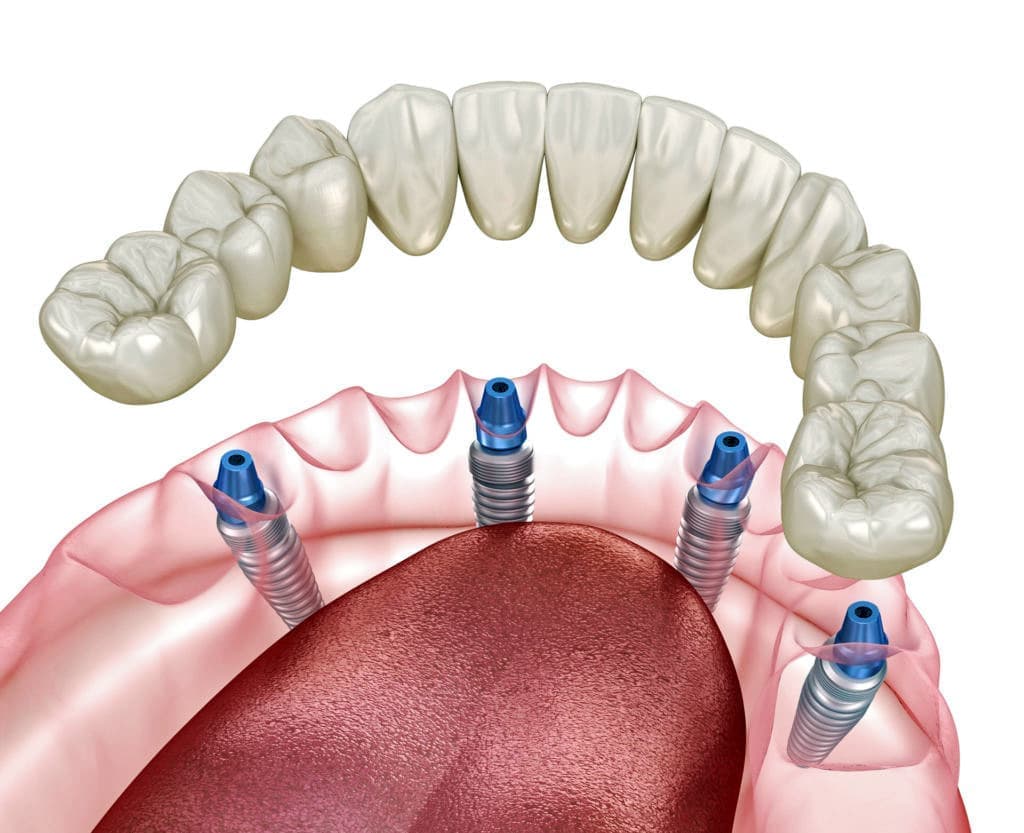

オールオン4は、奥のインプラントを骨のある部分へ斜めに埋め込み力を広く均等に分配することにより、最小4本のインプラントで全ての人工歯を支えることができる術式です。

手術による身体的負担や費用の負担なども最小限に抑えることができます。

※上顎の場合は4本で支えきれない事があり、インプラントの本数追加が必要な場合もあります。

※顎の骨の状態によっては下顎であってもインプラントの本数追加が必要な場合もあります。

被せ物はチタンフレームに組んだジルコニアを使用いたします。